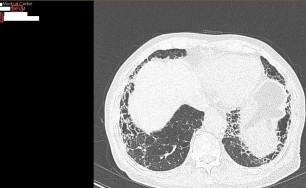

이러한 면역체계의 과민 반응이 기관지에 생기면 기관지벽이 두꺼워지고 그로 인해서 직경이 좁아지게 됩니다.

즉 천식은 기도 통로가 좁아지면 공기가 원활하게 지나가지 못하므로 호흡이 어려워져서 기침, 천식음(쌕쌕 거리는 소리), 호흡곤란, 가슴답답 등이 반복적으로 발생하는 질환입니다.